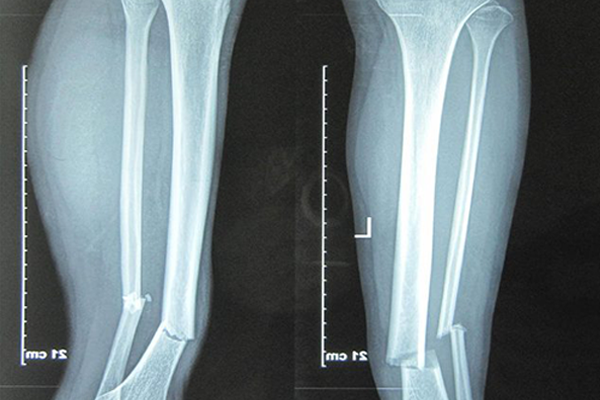

Để quan sát được rõ nét và chính xác quá trình liền xương, các bác sĩ sẽ chỉ định người bệnh tiến hành chụp X-quang vị trí gãy để thấy rõ tình trạng hiện tại để đưa ra những kết luận chính xác.